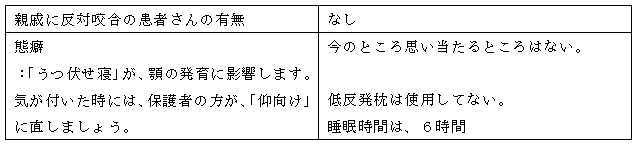

下の歯並びは気にならないが、下の顎が前に出てきた感じがし、本人が気になり始めた。以前、西村歯科で反対咬合をムーンシールドで治した。(6か月~1年間だと思う。)

定期検診で通院していた「〇〇こども歯科」で、今まで気にならなかったが、前歯が「ハの字」・スペース不足を指摘受ける。そこでは、顎を小学六年生まで拡げることが出来るが、歯を並べる事は出来ないと言われた。顎を拡げても歯を並べることが出来ないと困るので、〇〇君のお母さんに紹介頂いて西村歯科医院を受診。

本人が機嫌が悪い時があるので、取り外しの装置だと、毎日装着できるか?心配あり。

固定性(取り外し不可)の矯正装置を希望します。